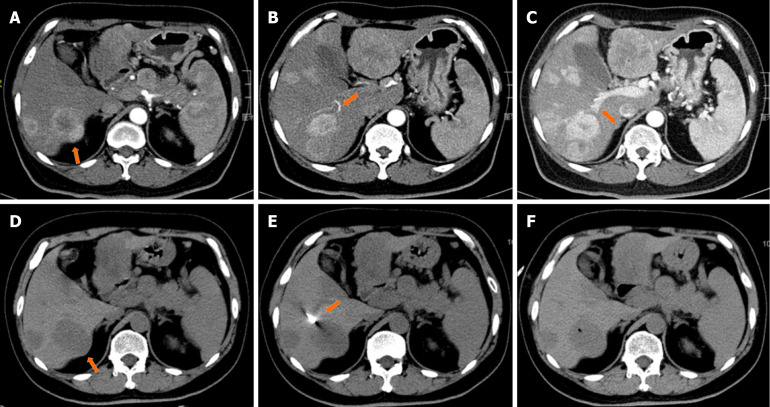

Methods: We retrospectively investigated 92 patients with liver metastases from GEP-NETs via PCT-CNB, 76 patient samples from the liver and primary sites, and 16 from the liver and secondary liver sites. Ki-67 immunohistochemistry was performed for tissue sampling, and grading classifications were determined. Intertumor grading classification heterogeneity and associated changes in patient survival outcomes were also evaluated.

Results: No procedure-related mortality was recorded during or after biopsy. In 37/92 patients (40.2%), the grading classifications changed: The grading increased from G1 to G2 in 13 patients, from G1 to G3 in 2, and from G2 to G3 in 14; the grading decreased from G2 to G1 in 5 patients, from G3 to G1 in 1, and from G3 to G2 in 2. Patients with G1 or G2 disease had better progression-free survival and overall survival (OS) outcomes than those with G3 disease did (P = 0.001 and P < 0.001, respectively). The 5-year and 10-year OS rates for stable G2 patients were 67.5% and 26.0%, respectively, decreasing to 46.4% and 23.2%, respectively, among G2 patients whose grade increased (P = 0.016).

Conclusion: The PCT-CNB of liver metastases from GEP-NETs differed in grade between the liver tumor and primary site/secondary liver metastases. Additionally, when grading increased from G2, the OS rate significantly decreased.